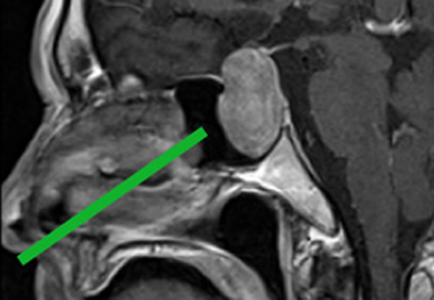

下垂体は脳の下についている約8mⅿの小さな組織ですが、様々なホルモンを分泌し体の調子を整える大切な役割があります。下垂体腫瘍の種類によってはホルモンが出過ぎて、高血圧や糖尿病を合併し、顔や体格の変化も来す事があります。腫瘍が大きくなると視神経を圧迫して視野が狭くなる事もあります。各々の腫瘍によって切除方法が異なり、時に手術そのものが不要な場合もあります。北大病院では内分泌内科と連携し、最適な治療を提供しています。

かつては開頭術や顔面の切開を行って手術が行われていました。最近は高画質の内視鏡を鼻から挿入して大小の重要な血管や神経を守りつつ腫瘍切除を行います。下垂体腫瘍は鼻腔の奥の頭蓋底部に存在しますが、腫瘍の拡がり方に応じて、骨を開ける範囲を拡大した方がより安全に摘出できる場合もあります。北海道大学では、時に耳鼻科医の協力のもと、複雑な手術を安全確実に行うようにしています。